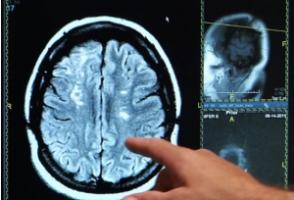

Actualité publiée il y a 10 années 3 moisAVC: Vite redonner avec un masque, de l'oxygène au cerveau

Actualité publiée il y a 10 années 3 moisEn France, on compte un AVC toutes les 4 mn. Cette étude d‘une équipe française de l’Inserm, publiée dans la revue Brain, montre qu’un geste tout simple ...

AUTISME: Un nouveau biomarqueur enfoui dans un pli du cortex

Actualité publiée il y a 10 années 3 moisCERVEAU: L'horloge neurale qui rythme notre vie quotidienne

Actualité publiée il y a 10 années 3 moisAVC: 73% des jeunes adultes en ignorent encore les signes